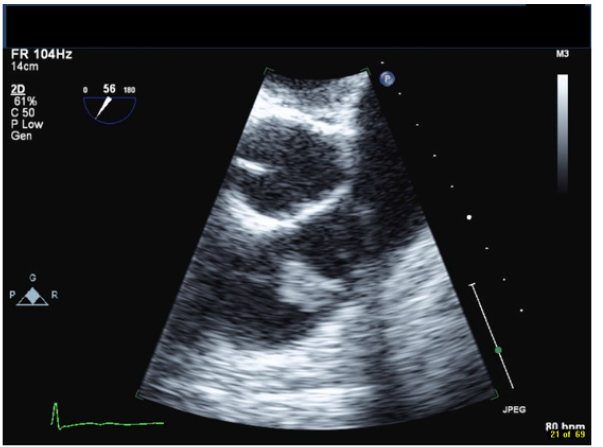

A 42-year-old male with a history of chronic nephrolithiasis presented to the hospital after neighbors found him unconscious at home. On initial evaluation, he was febrile (38.9) with blood pressure of 120/104mmHg. He was severely hypoxic with a sinus rate of 90 beats/minute. His examination revealed multiple abrasions, and he was minimally responsive with a holosystolic murmur at the apex. His electrocardiogram showed normal sinus rhythm with no acute ST-T wave changes. Laboratory data revealed a white cell count of 17.4/nl, platelet count of 109/nl, lactate level of 4.8 mmol/l and creatinine of 1.57mg/dl. Computed tomography of the head revealed multiple regions of acute infarction involving the right inferior cerebellum, left occipital lobe with mass effect on the left occipital horn. He underwent a transthoracic echocardiogram that showed vegetations on both the mitral and aortic valve. He underwent a trans-esophageal echocardiogram, which demonstrated multiple vegetations on the mitral (Figure 1), aortic (Figure 2) and pulmonic valves (Figure 3) with severe pulmonic, mitral and aortic insufficiency (Figure 4 & 5). Despite negative urine cultures, serial blood cultures grew Aerococcus urinae and he was given appropriate IV antibiotics. He was evaluated for possible valvular surgery and was deemed to be a poor surgical candidate. He later developed splenic and renal infarcts followed by significant hemodynamic instability requiring vasopressors and ultimately succumbed to his illness after he developed multi organ failure and disseminated intravascular coagulation.